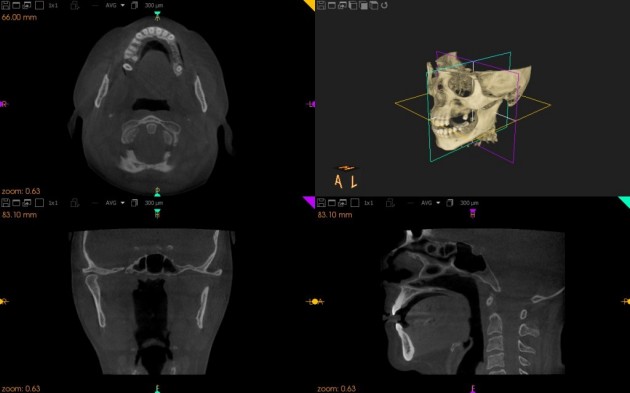

A tizedmilliméteres pontossággal dolgozó eszköz három dimenzióban képes megmutatni az állkapocs szerkezetét, és egyedülálló lehetőségeket kínál a fogorvosoknak.

A 3D CT-vel világosan megállapítható, hogy milyen vastag és milyen sűrűségű az adott területen a csontszerkezet, valamint jól láthatóak a környező anatómiai képletek pontos lefutásai is, ezért szinte minden esetben hasznosabb, mint az intraorális vagy a panorámaröntgen.

Miközben egy panorámaröntgen-képet csak két dimenzióban látunk, addig a 3D CT-vel váltogathatjuk a szeleteket, és oldalról is megnézhetjük, hogy a páciens milyen egészségügyi állapotban érkezett meg a klinikára; ha például a csont túl vékony az implantáláshoz, vagy egy kiterjedt cisztát állapítanak meg az érintett területen, akkor a műgyökér beültetését már nem lehet elvégezni.